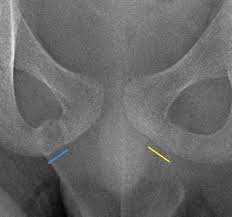

Ara Kassarjian Md Frcpc On Twitter Companion Case To Mskfellowship X Rays Of Ischiopubic Synchondosis Asymmetry Red Also Called Van Neck Odelberg Disease Thought To Also Be Associated With Hamstring Ischial Tuberosity Stress Injuries Yellow